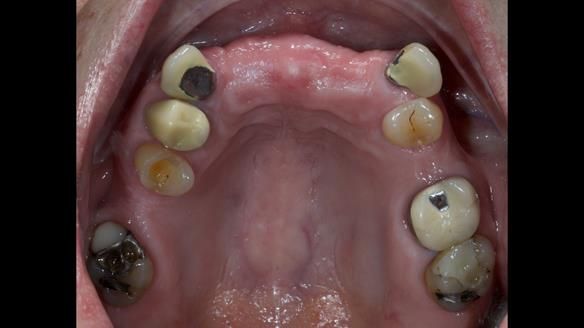

This is one of those cases that reminds me why I love removable prosthodontics. Pam was an absolute joy to treat — we were on the same page throughout. Her old upper flexible denture was loose, uncomfortable, and unaesthetic. We replaced it with a carefully designed metal-based upper partial denture/splint and new porcelain-bonded-to-zirconia (PBZ) crowns for the canines. The result is stable, comfortable, and natural-looking.

- Diagnosis and plan – Flexible upper denture ill-fitting with poor stability, retention, and appearance. Plan: metal-based upper partial denture/splint with lighter porcelain-bonded-to-zirconia crowns on UR3 and UL3.

- PBZ crowns provided – prepare, temporise, and make impressions for zirconia-bonded crowns (UR3, UL3).